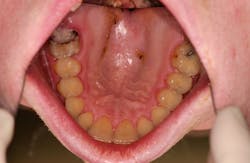

The patient self-reported a height of 5’5” and weight of 125 pounds, BMI 20.8. Oral examination showed a fully dentate individual. Mandibular third molars Nos. 17 and 32 were partially erupted, and both exhibited signs of pericoronitis with negative lymphadenopathy. Her dental history included several amalgam restorations on her posterior teeth. A 4 mm in diameter, erythematous, nonulcerated lesion was noted on the palate (figure 9).

When the patient was questioned about the history of the lesion, she stated that she had just entered a treatment facility for BN. She further stated that she purged three or four times daily and she noticed a slight irritation in the palate but had not noticed the lesion. The patient was referred to the UTSD Oral and Maxillofacial Surgery Department for extraction of teeth third molar teeth Nos. 1, 16, 17, and 32. The patient did not appear for her appointment and was lost to recall.

Dental management includes addressing any soft tissue lesions and dental erosion with the patient and discussing possible causes for the periomolysis, and a discussion of referral to an eating disorders clinic if needed. As we see in case report 2, the patient’s BMI falls within the normal range. It is, however, the palatal lesion that leads to the discussion of BN, without which might not have happened since the enamel erosion had a mild presentation and was not added to the medical history originally.